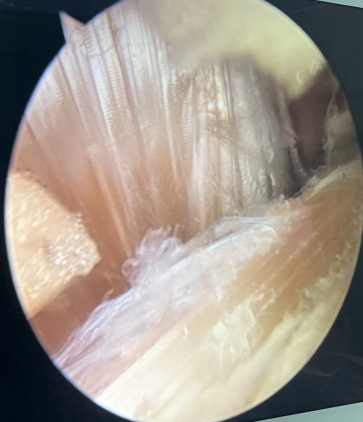

▲取自体双侧肌腱、编织新肌腱

▲术中精细操作,重建膝关节功能